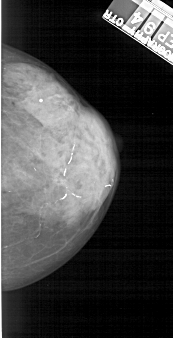

A_1223_1.LEFT_MLO

LEFT_MLO LINES 5026 PIXELS_PER_LINE 2491 BITS_PER_PIXEL 12 RESOLUTION 43.5 OVERLAY

FILE: A_1223_1.LEFT_MLO.OVERLAY

TOTAL_ABNORMALITIES 1

ABNORMALITY 1

LESION_TYPE CALCIFICATION TYPE PLEOMORPHIC DISTRIBUTION CLUSTERED

ASSESSMENT 4

SUBTLETY 4

PATHOLOGY MALIGNANT

TOTAL_OUTLINES 1

BOUNDARY